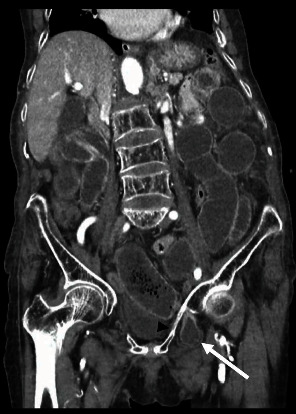

Obturator hernias, though rare, are clinically significant abdominal hernias, predominantly affecting elderly, thin women, with an estimated prevalence of less than 1%. The primary treatment involves surgical intervention to reduce and repair the defect, either through laparotomy or laparoscopy, with bowel resection needed in up to 75% of patients. Here, we present the case of an 83-year-old woman presenting with abdominal pain and a history of constipation. An abdominal computed tomography scan demonstrated a left obturator hernia with small bowel obstruction. Successful reduction of the hernia was achieved, albeit requiring intestinal resection via an open surgical approach. Subsequently, the patient achieved complete recovery.